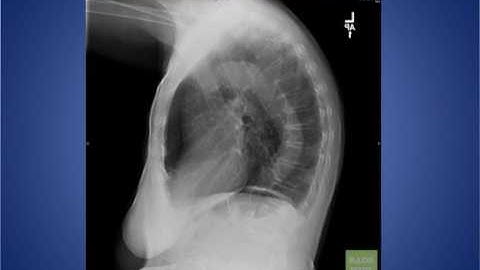

Lateral CXR path part 2 - "EM in 5"